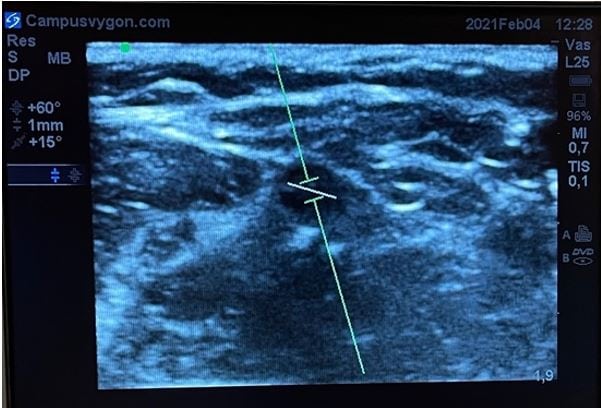

“Es esencial, para obtener una buena señal Doppler color, vascular el transductor y conseguir un ángulo menor de 60º obteniendo una medición óptima con una angulación de 30º o menor”.

Posteriormente, angulamos el transductor entre 30 a 60º o bien hacia la parte distal del cuerpo (hacia la mano), o hacia la parte proximal (hacia la cabeza). Por último, volvemos a activar el modo doppler color para que comience el análisis, obteniendo una tonalidad roja al identificar el flujo que fluye hacia el transductor o azul si éste, se aleja.

Cuando se estudia un vaso longitudinalmente con modo doppler color, puede ser útil emplear la opción de angulación de la caja de color, de tal manera que ahora los ultrasonidos se emitan angulados desde la sonda.

Esto facilita la identificación del vaso, sin tener que bascular la sonda en la piel del paciente. Teniendo en cuenta la posición de la muesca del transductor respecto a la pantalla y la angulación del ROI, podremos discernir la dirección del flujo estudiado mediante la misma regla: el flujo que se acerca al transductor será de color rojo y el que se aleja de color azúl.

Manteniendo la exploración en modo B, activamos el modo doppler espectral. A continuación, colocamos el volumen de muestra (identificado como dos líneas paralelas y perpendiculares al eje del haz de ultrasonidos) en el interior del vaso que se pretende estudiar. El tamaño del volumen de muestra debe ser proporcional al calibre del vaso a estudiar.

Angulamos el transductor entre 30 a 60º o bien hacia la parte distal del cuerpo (hacia la mano) o hacia la parte proximal (hacia la cabeza), y por último volvemos a activar el modo doppler espectral para que comience el análisis de velocidades.

Si el espectro de velocidades se sitúa sobre la línea base significará que el flujo del vaso sanguíneo estudiado se dirige hacia el transductor. Por el contrario, si el espectro de velocidades se sitúa por debajo de la línea de base, significará que el flujo del vaso sanguíneo estudiado se alejará del transductor.

Además del sentido de la sangre, la morfología del espectro nos informará del carácter del flujo del vaso estudiado. Así, si el flujo es pulsátil, habitualmente se tratará de un vaso arterial. Mientras que si el flujo es continuo o poco pulsátil, habitualmente se tratará de un vaso venoso.